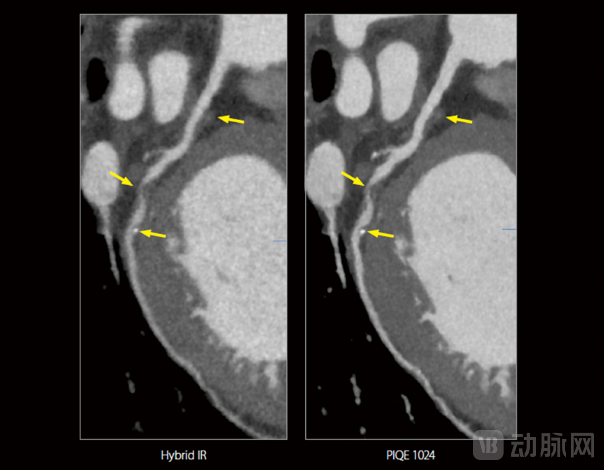

在冠心病的诊断中,正性重构是冠状动脉斑块破裂高风险的标志之一。如果不能准确识别血管的正性重构情况,医生可能会低估患者发生急性心血管疾病(如心肌梗死)的风险,导致漏诊或误诊。上图是PIQE图像协助医生捕捉到的一名冠心病患者随访诊断中的极微小病灶:可以看到,与传统混合迭代图像(左)相比, PIQE图像(右)更清晰地显示了LCX(左回旋支,冠状动脉的主要分支)中存在软斑块导致的严重狭窄(>70%),中段血管向外/正性重构,并显示该狭窄处位于第一钝缘支前方约10mm处,狭窄处远端存在一个微小钙化斑块。针对这一新发病变,医生及时调整了治疗方案。